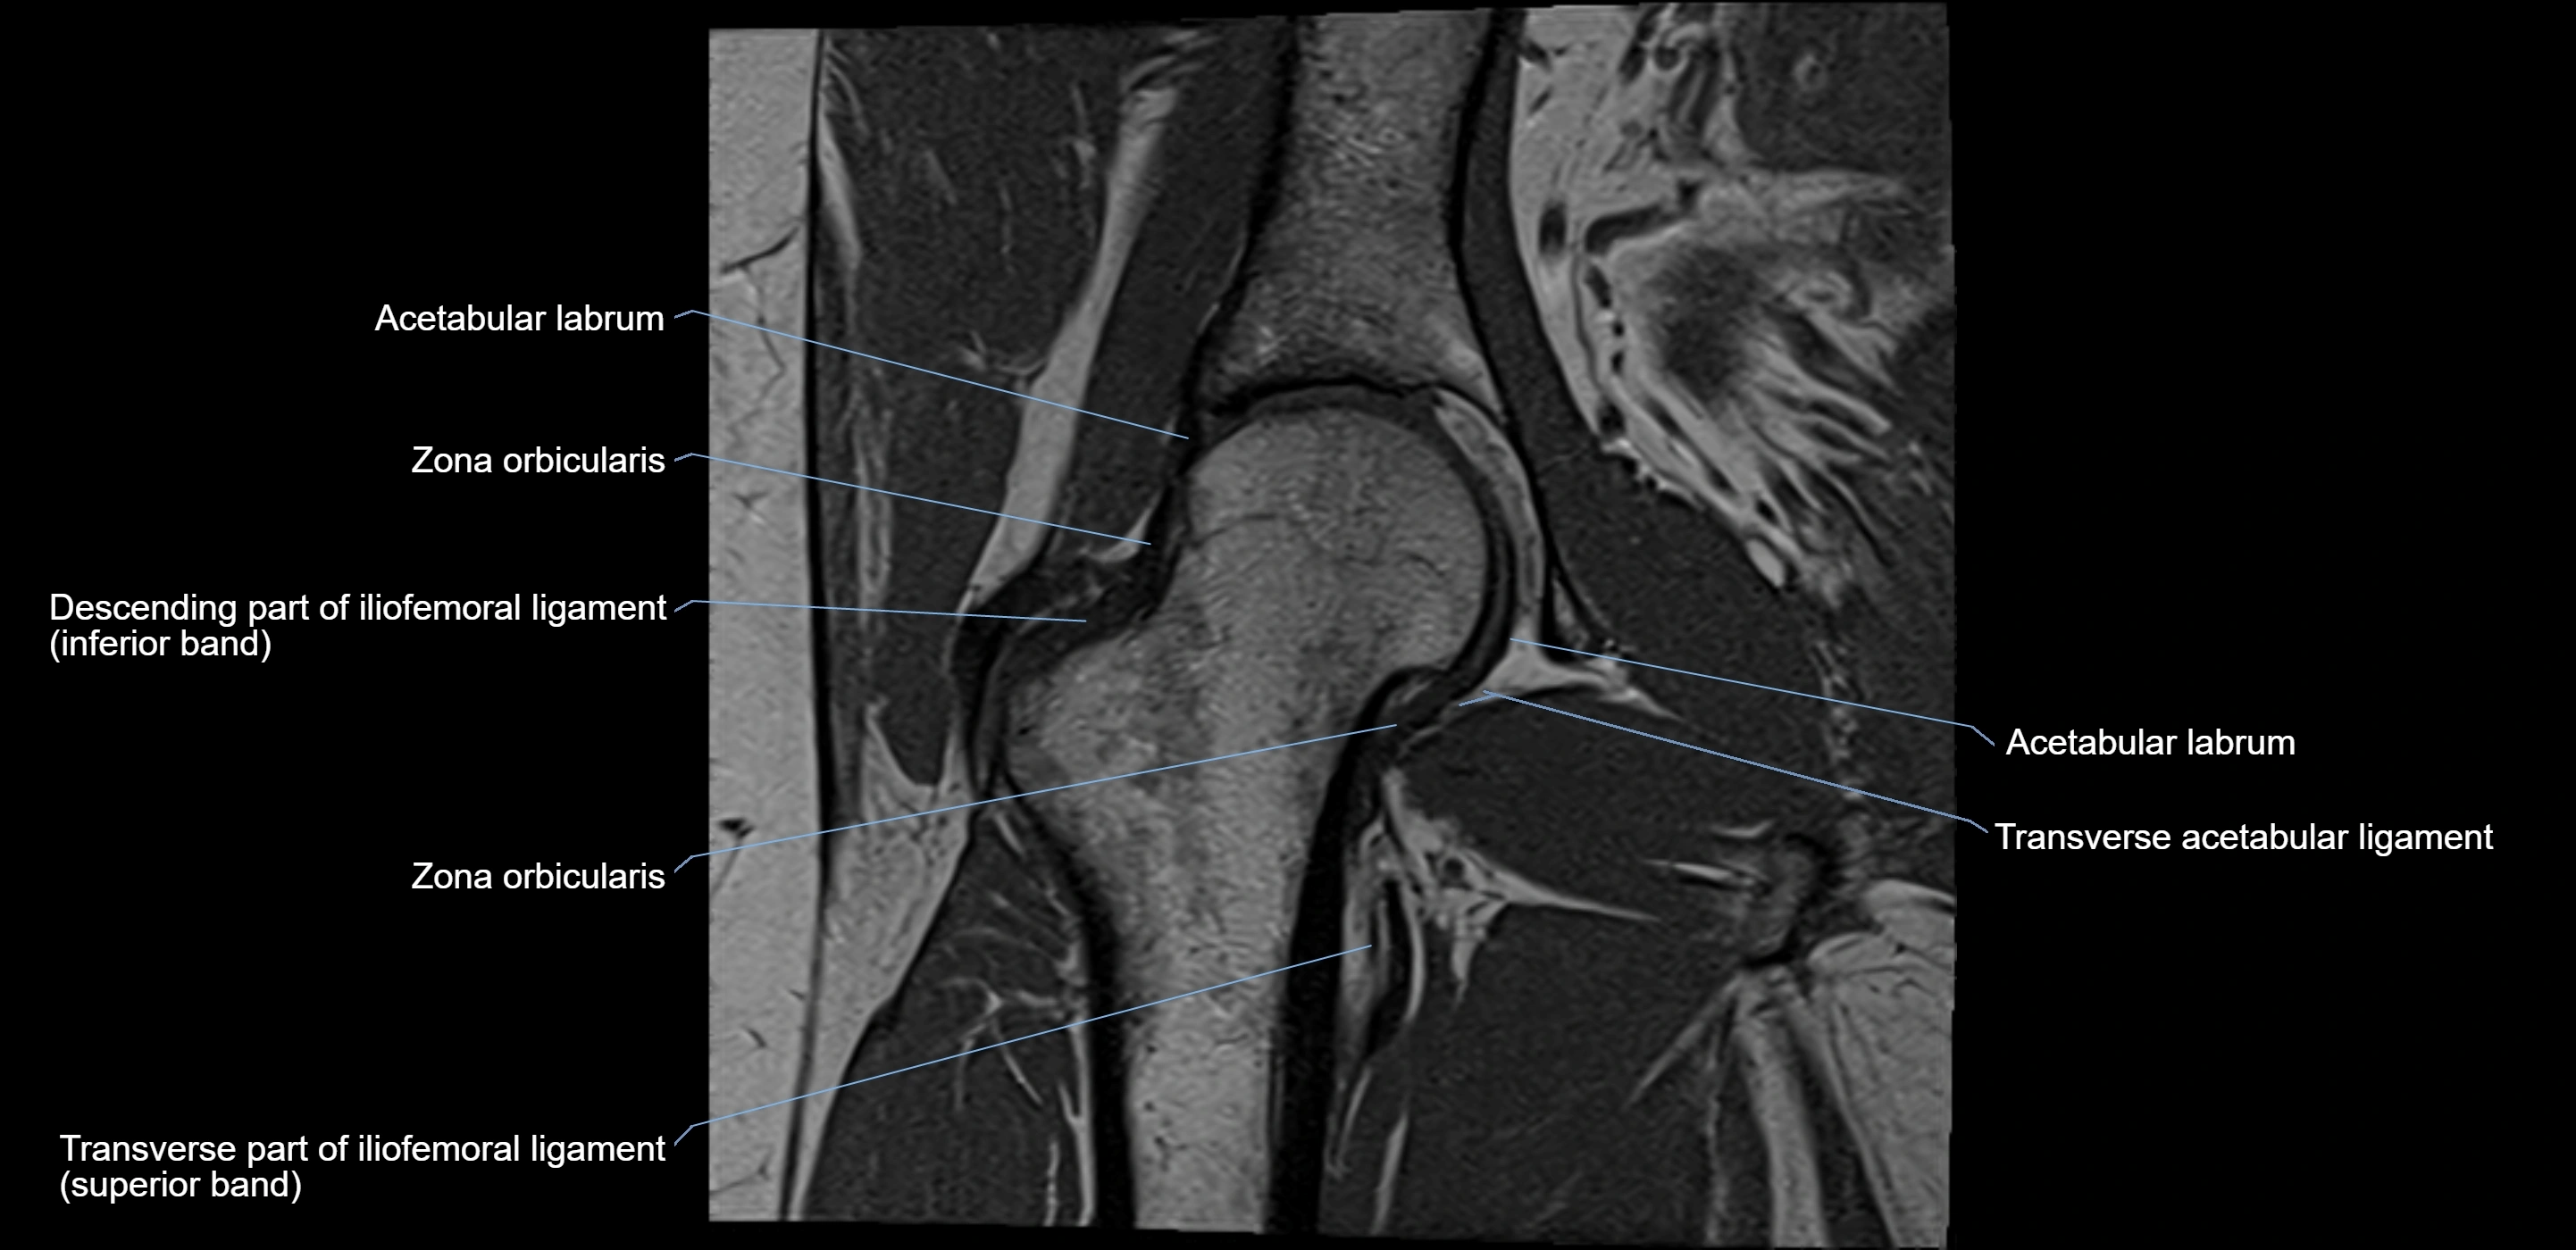

Structure and Relations

• Superior and anterior labrum: thickest portions, stabilizing against anterior dislocation

• Inferior labrum: blends with the transverse acetabular ligament bridging the acetabular notch

MRI Appearance

T2-weighted images:

• Labrum: low signal intensity (dark)

• Joint fluid: bright, making labral tears visible as fluid extending into or around labrum

MRI image

image